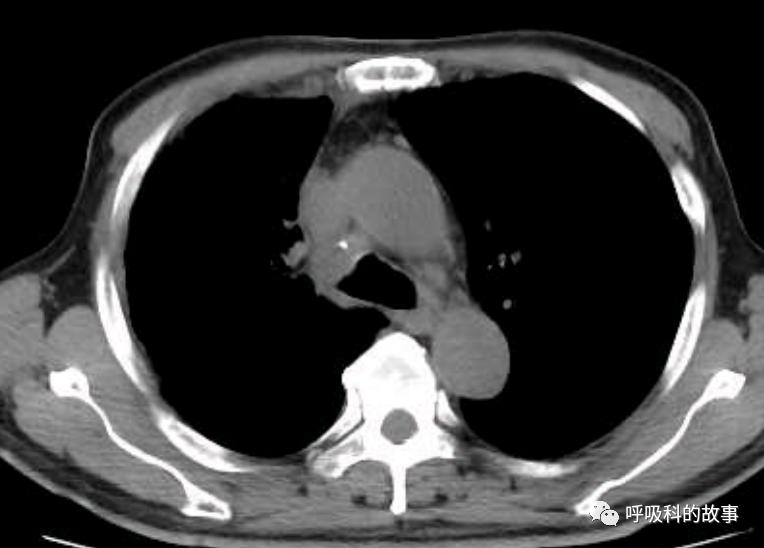

当时我们也曾经考虑给病人做淋巴结活检,但再次遭到患者的拒绝,由于患者体温正常,症状好转,我们也没有坚持。经过了两个多月的伏立康唑治疗,肺部影像基本吸收。

纵隔淋巴结也明显缩小了